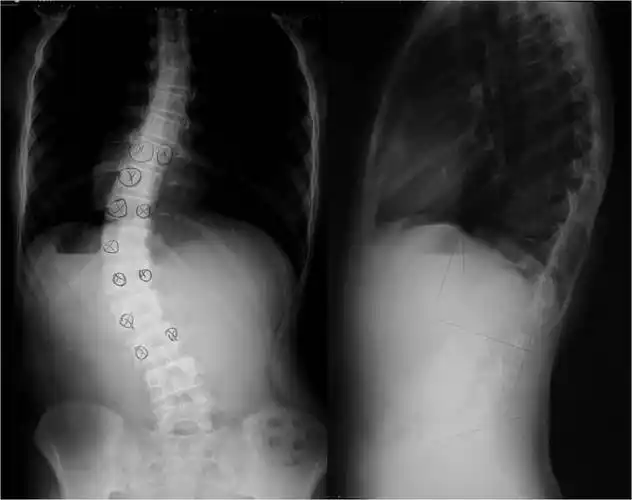

脊柱侧弯在青春期里度数增长的速度有多快?

青少年特发性脊柱侧弯 典型病例2 - 好大夫在线